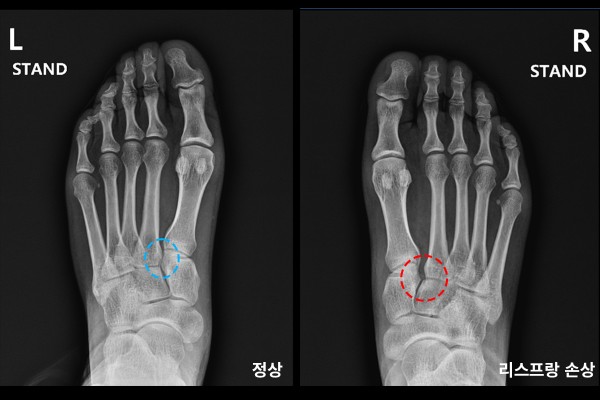

신체검진상 발등과 발바닥쪽에 피멍이 들어있음을 확인하였고, X-RAY 사진을 확인했을 때 정상적인 간격의 좌측 발에 비해 우측 발은 내측 설상골(쐐기골)과 제2 중족골 기저부(뿌리부) 사이가 벌어져 있는 것을 확인하였습니다.